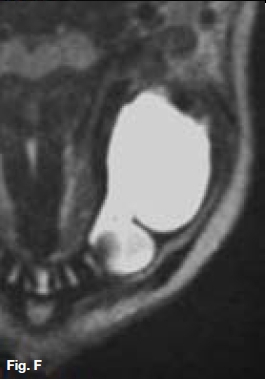

The cropped pantomograph (Fig.B) shows a multilocular radiolucency of an expansive tumour containing varying calcifications. Figures D&E show a well demarcated multilocular lesion in the body/ramus region of the left mandible, with two displaced molar teeth, resorption of the roots of 34 and 35 and tooth-like calcifications at the borders of the lesion. The coronal T2 MRI image (Fig.F) shows a multilocular hyper-intense lesion, with no discernible calcifications. Diagnosis: the rare tumour, odonto-ameloblastoma (OA), first reported by Kemper and Root (1944). Shafer ef al (1983) described this as an odontogenic neoplasm of mixed tissue origin, consistent with both ameloblastoma and odontoma. Histologically, a typical ameloblastoma component whilst the odontoma element may be either compound or complex. Shafer et al (1983) emphasized that this is one neoplastic process with relatively highly undifferentiated tissues. Occurring most commonly in the second decade of life, it may vary in size. Smaller lesions occur between the teeth, confined to the alveolar bone between the crest of the ridge and the teeth apices (Figs. A,B&C). Buccal expansion of the cortex is common, even for smaller lesions. The odontoma component presents various stages of development, early lesions being radiolucent with radiopaque flecks. More mature lesions are better developed odontoma, resembling teeth or as a nonspecific complex odontoma mass. Importantly, this is an aggressive tumour, treated precisely as an ameloblastoma. The differential diagnosis should include: ameloblastic fibro-odontoma, Pinborg tumour, calcifying odontogenic cyst and adenomatoid odontogenic tumour.